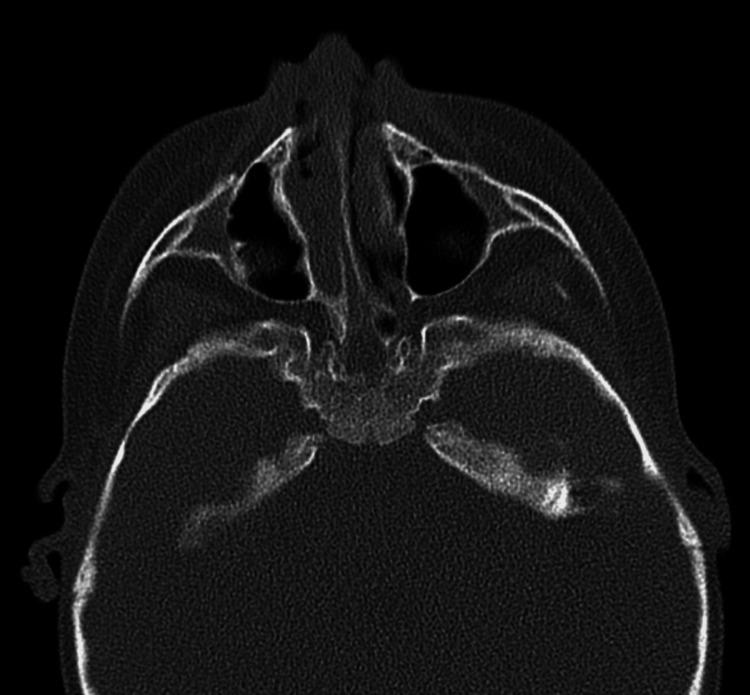

Introduction Choanal atresia (CA) is an uncommon congenital anomaly. There are various syndromes that are associated with CA. The purpose of this study is to determine the differences in CA's presentation and outcome when associated with other congenital anomalies and syndromes. Method This is a retrospective review study of all children (18 years and younger) who underwent CA repair in a tertiary referral healthcare center from January 2005 to April 2022. Demographics, comorbidities, radiological testing, operative reports, and outpatient reports were collected. Success was determined as a child with bilateral patent choana that is able to breathe from both nostrils comfortably. Result Twenty-four patients met the criteria for inclusion in this study. Bilateral CA was present in 15 (62.5%) patients. Mixed CA was the most common variant. There were various congenital anomalies in association with CA patients who are yet to be classified into a syndrome. The most common congenital anomaly was cleft lip and palate. Bony and mixed types were significantly associated with non-syndromic patients (p<0.05). Twenty patients (83%) were diagnosed with CA at age of less than one year, and four patients were diagnosed after one year of age. There were 36 surgeries performed on 24 patients, of which 27 were endoscopic and nine were using Hugher dilator. The overall success rate for CA repair was 50%. The median number of revisions per patient was 0.5. Conclusion CA is a challenging anomaly to repair. There are various factors that influence the outcome of children with CA. Otolaryngologists should counsel the patient and their families regarding possible need for revision especially in those with other craniofacial anomalies.